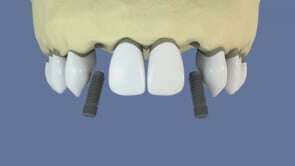

Retrouvez le sourire ! Grâce aux implants dentaires, solution pour stabiliser un bridge, remplacer un appareil dentaire, ou une dent. Lisez et contactez le cabinet dentaire des docteurs Brandt à Sarreguemines !